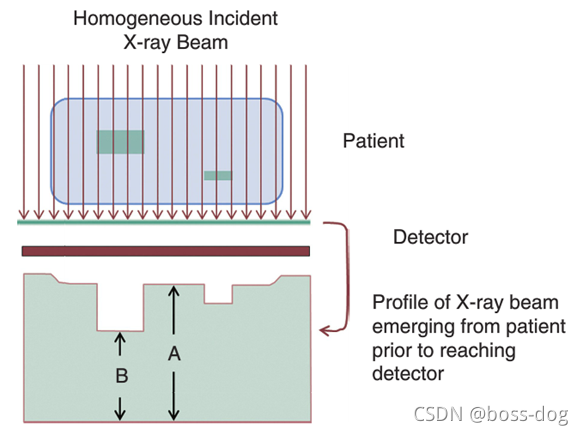

对比度

对比度是指图像上的差异、灰度之间紧密相邻图像上的区域。

对比度的分类:

1)对象本身得对比度

2)探测器(胶片或采集系统)的对比

3)显示成像的对比(给医生看的屏幕对比度怎么样)

X光穿过人体,如骨头吸收的多或者厚的组织吸收的X光多一点,薄的或者如空气、水等吸收X光少一点,则就会出现差别,它们的吸收率(吸收X光的强度)不一样,吸收率公式如下: